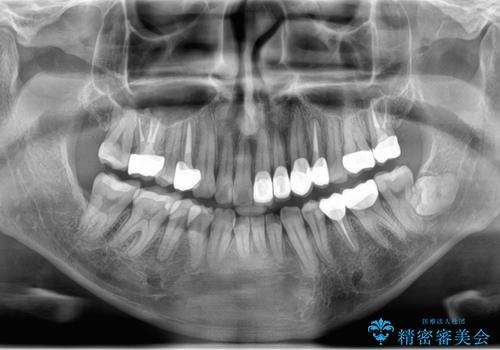

- 今装着されている全ての銀歯の除去、虫歯の治療、矯正治療を含めた総合治療を希望され来院されました。

放置すると大きくなりそうな虫歯をまず治療、矯正治療を行ったのち、全ての銀歯を除去しセラミック治療を行う治療計画としました。

長年の悩みであった虫歯や、噛み合わせ、歯並びの問題が解決でき喜んでいただくことができました。